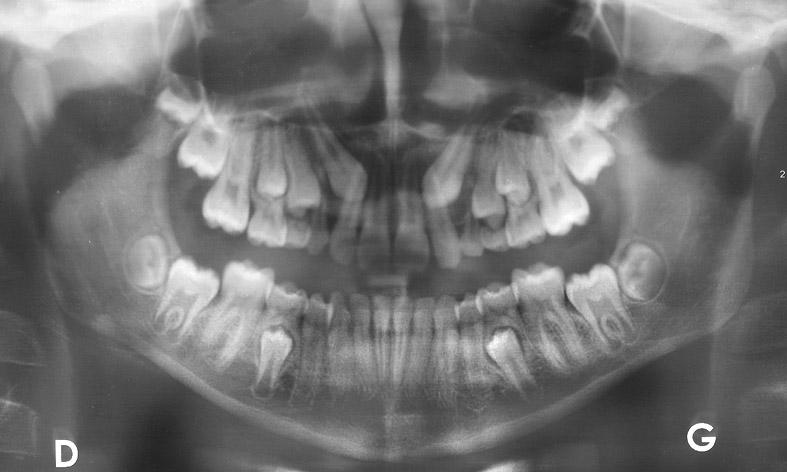

Agénésies dentaires

Environ 5% de la population présente l’absence d’une ou plusieurs dents, appelée agénésie.

Ce phénomène génétique est retrouvé en général chez plusieurs membres de la même famille, mais pas chez tous.

Le traitement consiste, soit à fermer l’espace de la dent absente, soit au contraire à aménager cet espace pour la pose d’un futur implant et d’une couronne. L’utilisation de bagues ou de gouttières est indispensable.

Canine incluse

Une canine définitive fait en général son éruption vers 11-12 ans, mais il n’est pas rare de voir une canine ne pas pouvoir sortir, la plupart du temps à l’arcade maxillaire, en raison d’un manque de place.

C’est pourquoi il faut commencer à s’en préoccuper dès 7-8 ans en élargissant la mâchoire supérieure, puis en faisant enlever les canines de lait si cela ne suffit pas.Malheureusement, malgré cela, les canines peuvent suivre un chemin oblique vers les incisives. Il faudra alors commencer à poser des bagues pour créer de la place, et si nécessaire, en dernier recours, ouvrir la gencive pour coller un bouton relié à un petit élastique pour pouvoir tirer sur la dent et lui permettre de faire son éruption.